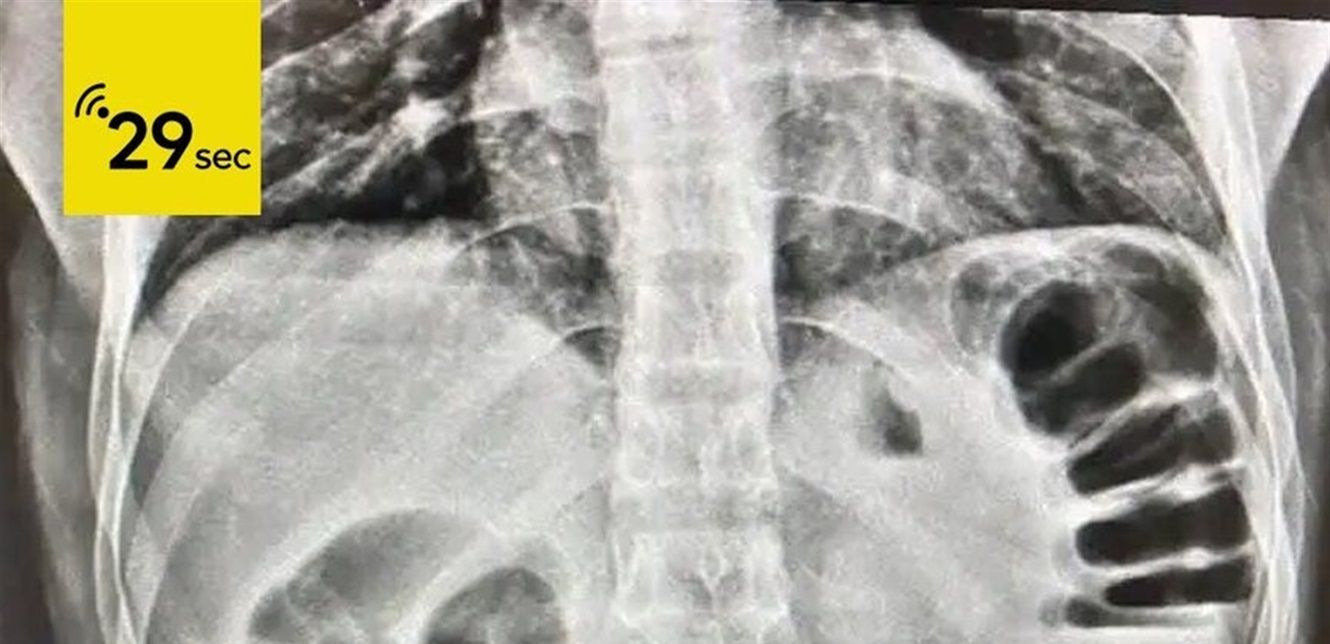

وأوضحت إدارة المستشفى أن الفحوصات بالأشعة كشفت وجود الهاتف داخل معدة المريض، ما تسبب في انسداد شبه كامل في القناة الهضمية.